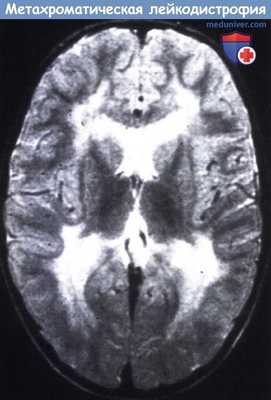

При всех трех типах заболевания на КТ и МРТ отмечаются изменения перивентрикулярного белого вещества с преобладанием поражения в лобной области. При ювенильной и взрослой формах заболевания U-волокна сохраняются, отмечается раннее поражение мозолистого тела, в пирамидном тракте могут выявляться признаки демиелинизации. Диагноз подтверждается на основании определения уровня ARSA и метахроматического материала в моче.

Метахроматическая лейкодистрофия

Метахроматическая лейкодистрофия — аутосомно-рецессивно наследуемая демиелинизирующая патология ЦНС, отличительной особенностью которой является метахроматическое окрашивание зон демиелинизации. В клинике преобладает задержка развития, парезы, судорожные приступы, экстрапирамидные и мозжечковые расстройства, нарушение зрения. В ходе диагностики проводится исследование цереброспинальной жидкости, уровня сульфатидов, активности арилсульфатазы А, КТ/МРТ головного мозга, генетические обследования. Возможна пренатальная диагностика. Лечение симптоматическое, в отдельных случаях проводится трансплантация пуповинной крови или стволовых клеток.

Диагностические мероприятия имеют комплексный характер и позволяют отдифференцировать метахроматическую лейкодистрофию от других нейродегенеративных заболеваний и других форм лейкодистрофии. Проводится люмбальная пункция, при исследовании цереброспинальной жидкости определяется повышенная концентрация белка, дефицит арилсульфатазы, белково-клеточная диссоциация. Электромиография выявляет увеличение длительности проведения нервных импульсов. КТ головного мозга визуализирует расширенные желудочки и определяет пониженную плотность белого церебрального вещества. МРТ головного мозга выявляет очаги демиелинизации.